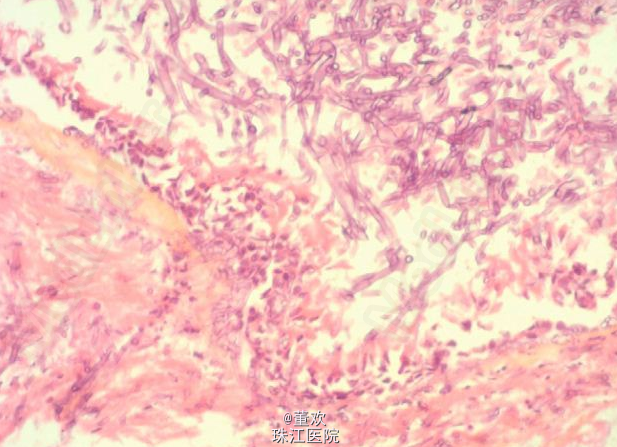

查体:双肺呼吸音弱,可问及大量湿性罗音。 辅助检查:支纤镜下可见气管支气管粘膜多处溃疡和坏死,支气管壁似乎有白色斑块附着和假瘤样病变。常规行苏木素 - 伊红染色后,之气管壁活检样本可见真菌菌丝侵袭浅表粘膜引起的弥漫的溃疡性炎症性气管支气管炎。具体图像如下。

诊断:暴发型侵袭性气管支气管曲霉病。 处理:对此类患者必须高度怀疑此病,纤维支气管镜结合对活检标本行快速的组织学检查,能加快该病的诊断进程,给予吸氧、祛痰、特异性抗炎等治疗。必要时行气管切开通气。